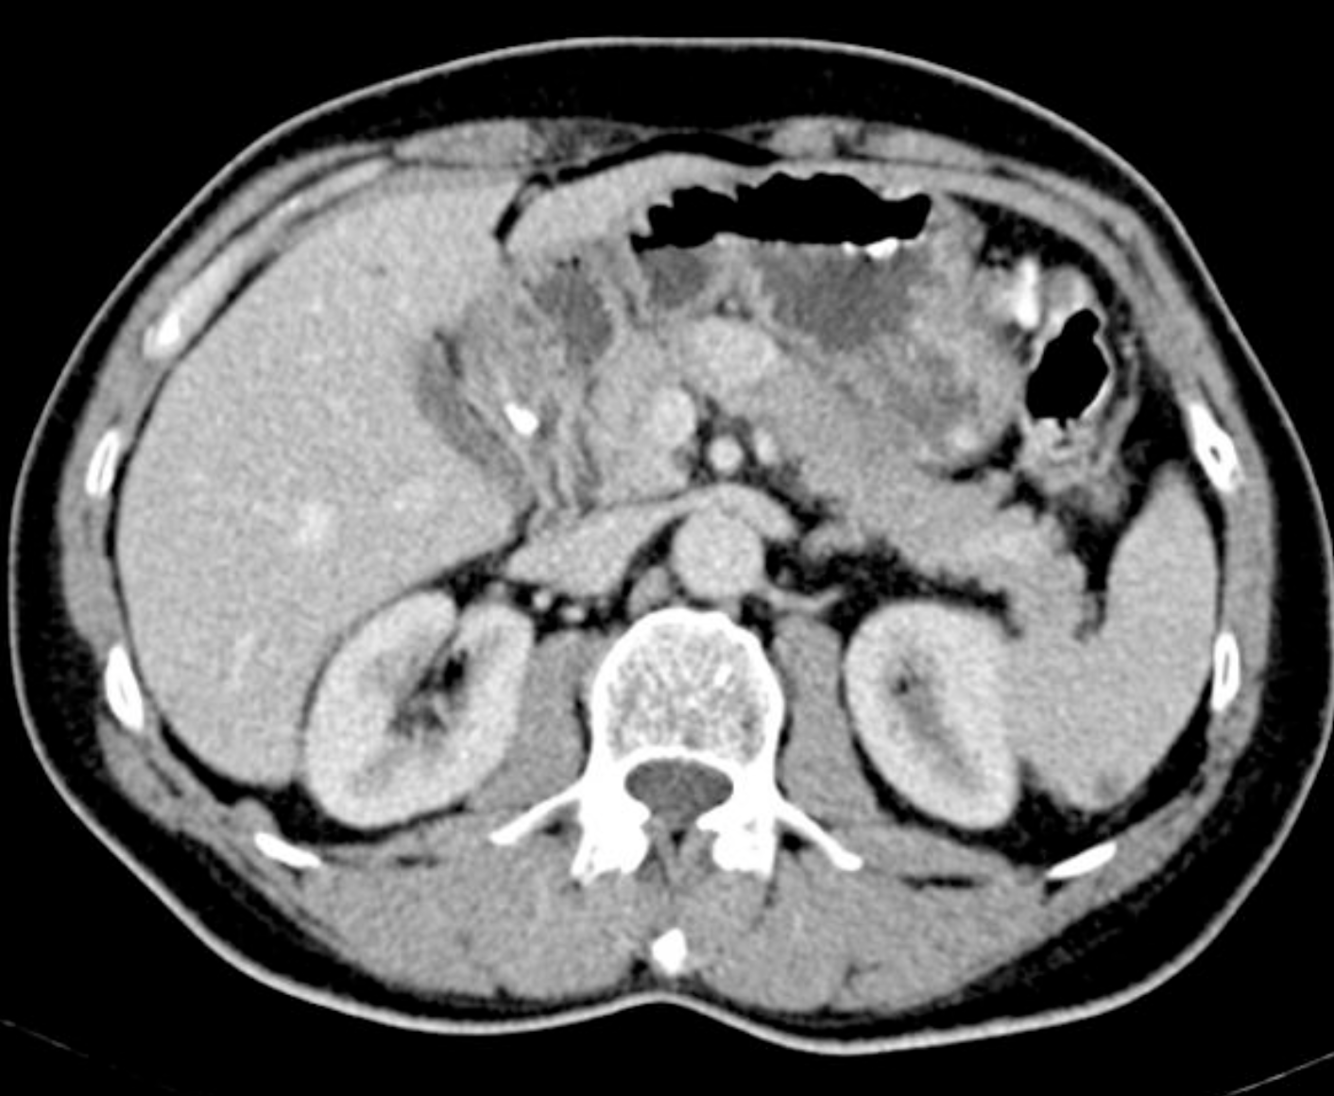

Single phase CT scan (multiphase scans not performed due to age of patient) demonstrates a diffusely enlarged pancreas with a “halo” like rim of hypoattenuating tissue which is smoothly marginated. Minimal peripancreatic fat stranding.

Associated splenic vein thrombosis, splenomegaly and cavernous transformation of the portal vein.